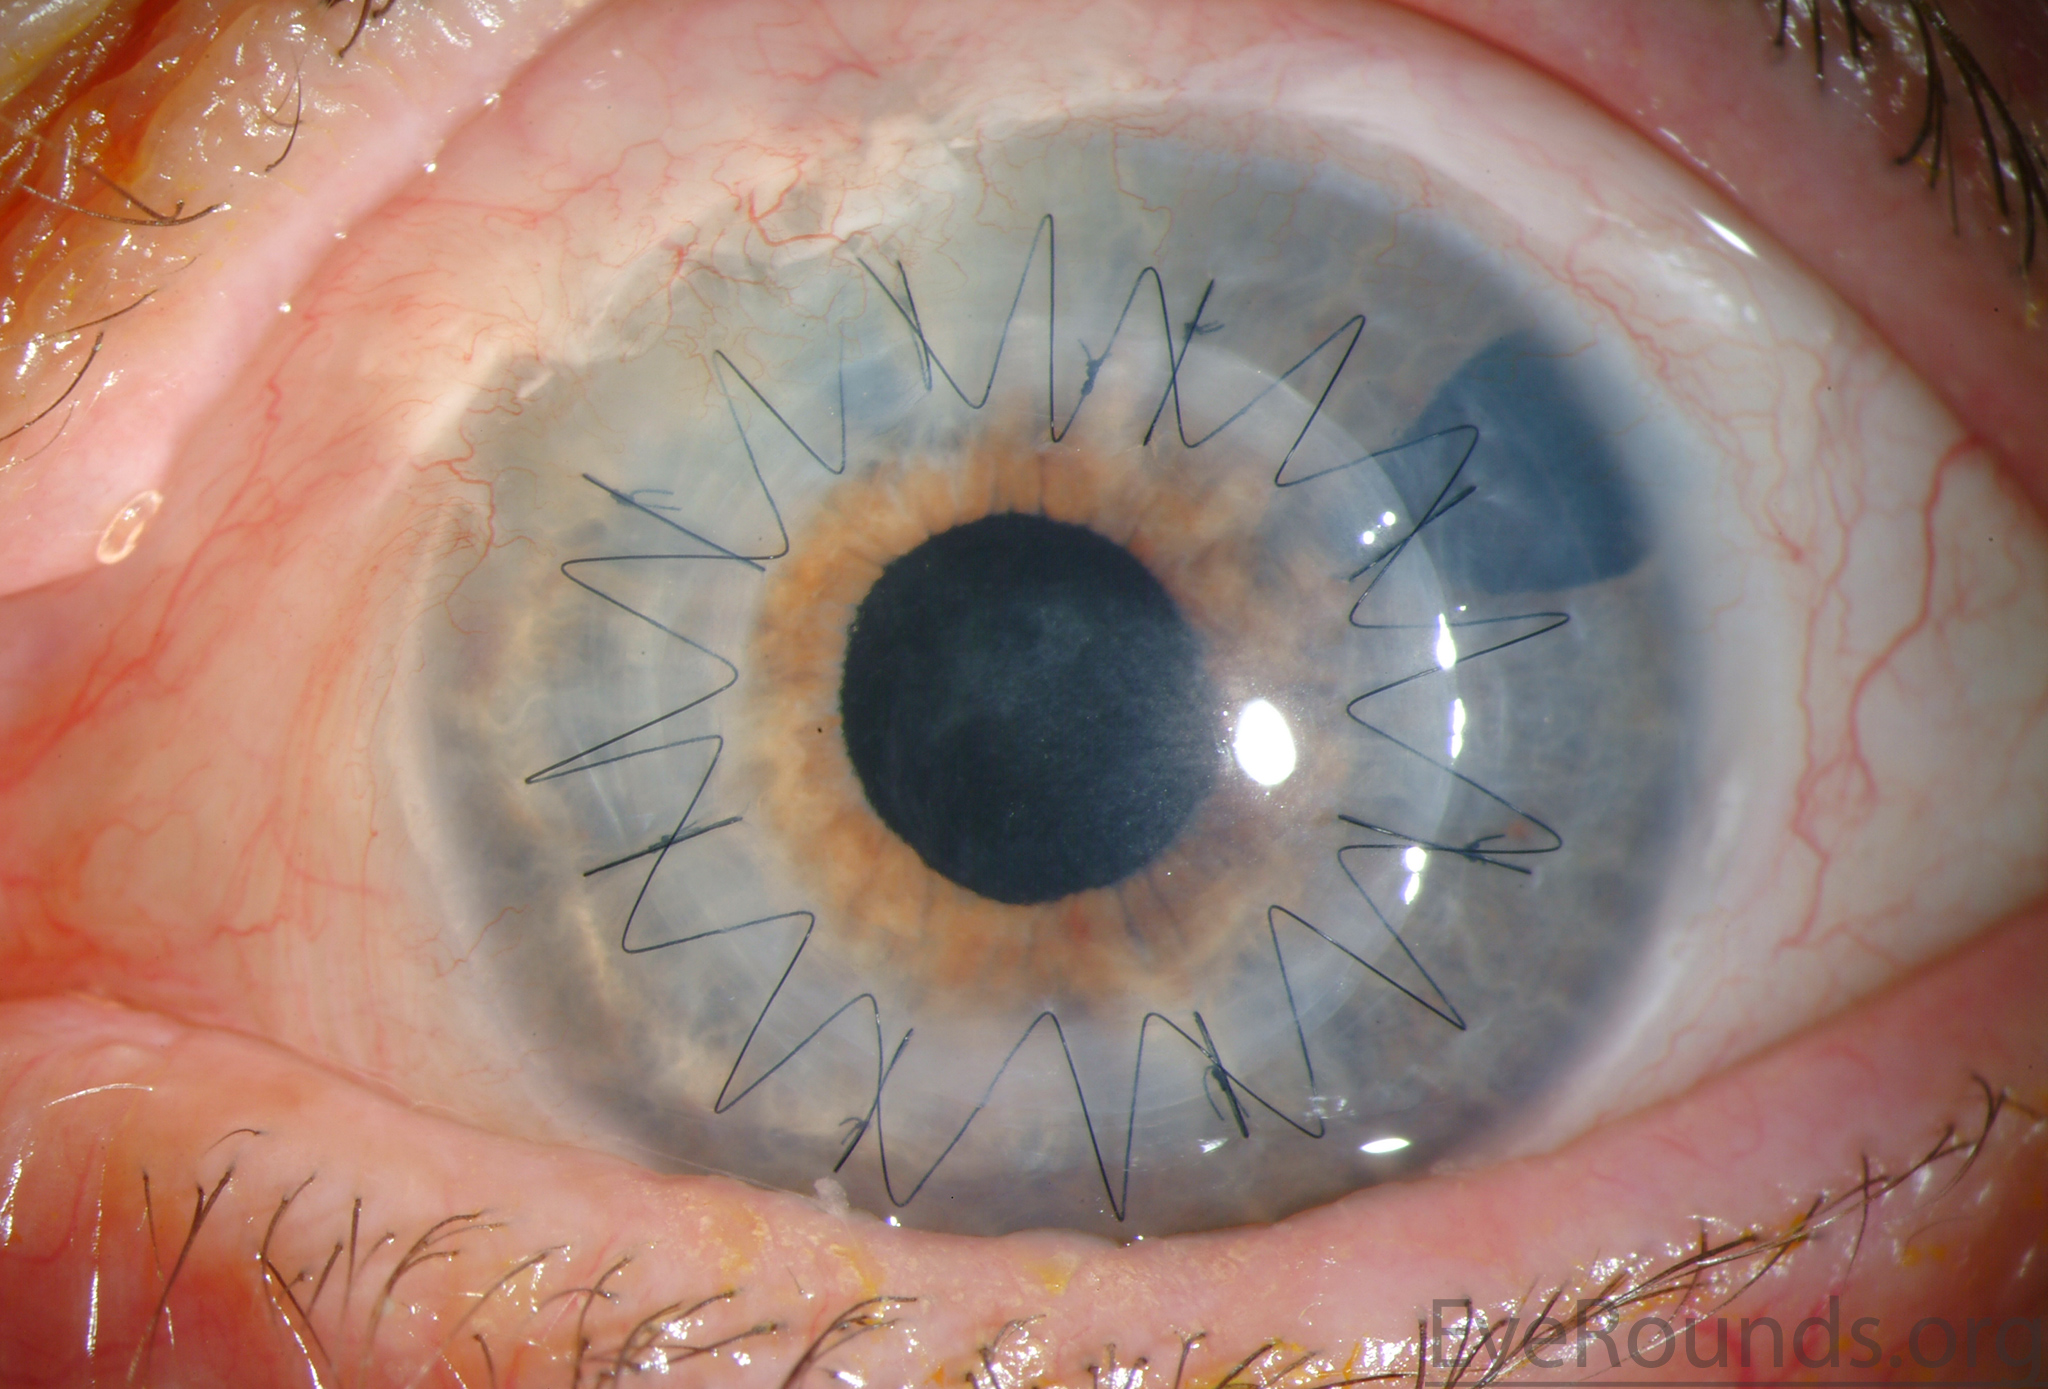

PK is a full-thickness transplant procedure, in which a trephine of an appropriate diameter is used to make a full-thickness resection of the patient's cornea, followed by placement of a full-thickness donor corneal graft. Interrupted and/or running sutures are placed in radial fashion at equal tension to minimize post-operative astigmatism (Figure 2). Later, the sutures are removed selectively to reduce the amount of astigmatism present. A transplant can last decades with proper care (Figure 3). While once the most prominent type of corneal transplant, PK has been supplanted by partial thickness techniques for endothelial dysfunction without significant stromal scarring. PKs are performed primarily for visually significant stromal scarring, opacities with an uncertain status of the endothelium or significant posterior corneal involvement, corneal ectasia (such as keratoconus and pellucid marginal degeneration, especially if there is history of hydrops), combined stromal and epithelial disease (such as Peters anomaly), and infectious or non-infectious corneal ulcerations or perforations (1, 14). A variant of the procedure, the mini-PK, can be used to treat more focal defects in the cornea (Figure 4).

DALK is a partial-thickness cornea transplant procedure that involves selective transplantation of the corneal stroma, leaving the native Descemet membrane and endothelium in place. A trephine of an appropriate diameter is used to make a partial-thickness incision into the patient's cornea, followed by pneumodissection or manual dissection of the anterior stroma. This is followed by placement of a graft prepared from a full-thickness punch in which the donor endothelium-Descemet membrane complex has been removed. The intention is to preserve the patient's Descemet membrane and endothelium. Similar to PK, the graft is secured with interrupted and/or running sutures (Figure 5) and these are then selectively removed post-operatively (Figure 6).